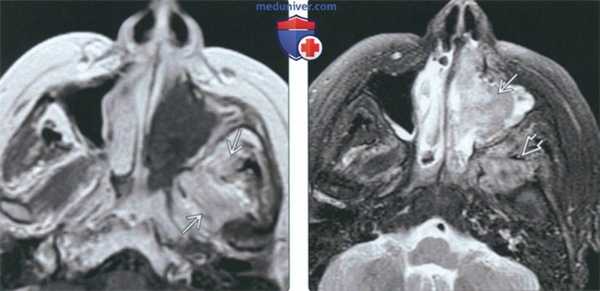

В рамках предоперационной подготовки для представления об объеме костной деструкции выполнена КТ околоносовых пазух. Обнаружена эрозия костного канала зрительного нерва слева, костного канала левой внутренней сонной артерии (рис. 1). Рисунок 1. Компьютерная томограмма ОНП (аксиальная проекция) больного Е. Затемнение обеих клиновидных пазух, дефекты костного канала зрительного нерва слева, костного канала левой внутренней сонной артерии (указано стрелками). Принято решение о необходимости эндоскопической сфеноидотомии с ревизией клиновидной пазухи и, при необходимости, удалении новообразования с последующим его гистологическим исследованием. Предоперационный диагноз: новообразование клиновидной пазухи. Паралитическое косоглазие слева.

Послеоперационный период гладкий. На 5-й день произведен туалет оперированной полости под эндоскопическим контролем. Для лучшего осмотра оперированной полости также использована модель ULYSS. На 7-й день после операции отведение левого глаза восстановилось на 80%, исчезла головная боль. При эндоскопическом исследовании соустье клиновидной пазухи слева широкое, функционирует, что подтверждено данными КТ (рис. 3). Рисунок 3. Компьютерная томограмма ОНП (аксиальная проекция) больного Е. на 7-е сутки после операции по поводу грибкового тела. Воздушность клиновидной пазухи полностью восстановлена, естественное соустье пазухи достаточного размера (указано стрелкой), что обеспечивает адекватную аэрацию пазухи в послеоперационном периоде. Однако в связи с частичным разрушением канала левой внутренней сонной артерии пациенту рекомендовано динамическое наблюдение.